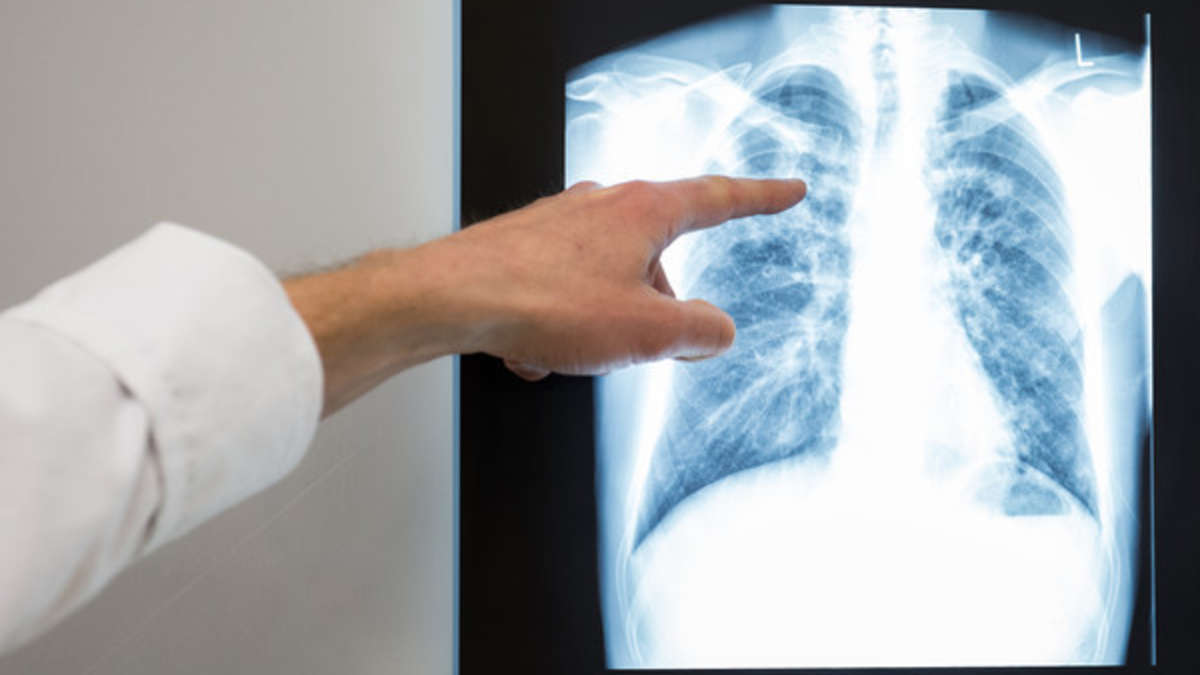

Туберкулез – широко распространенное в мире инфекционное заболевание, вызываемое различными видами микобактерий. Туберкулез обычно поражает легкие, реже затрагивая другие органы и системы. Инфекция передается воздушно-капельным путем при разговоре, кашле и чихании больного."50% населения являются носителями туберкулеза, а вероятность того, что инфекция перейдет из спящего режима в активный в течение жизни, составляет 10%", – написала Супрун в соцсетях. "Пока в странах с развитыми системами здравоохранения сосредоточены на раннем выявлении и амбулаторном лечении туберкулеза, в Украине система была сфокусирована на диагностировании уже тяжелых форм болезни и изоляции пациентов. Это стало одной из причин распространения устойчивых к лекарствам форм туберкулеза", – отметила Супрун. И.о. министра подчеркнула, что раннее выявление туберкулеза и регулярный прием лекарств позволяют полностью излечить его "даже без госпитализации". Ранее Супрун объяснила, что лекарства можно получить бесплатно у своего семейного врача.

Супрун ошарашила новостью: 50 процентов украинцев – носители туберкулеза

Исполняющая обязанности министра здравоохранения Ульяна Супрун у себя на странице в Facebook сообщила, что половина украинцев – носители туберкулеза.